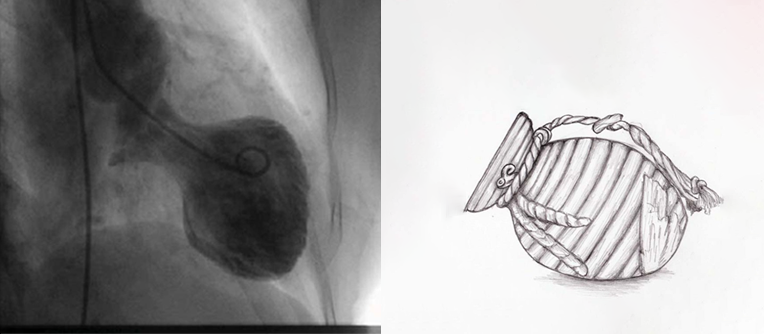

Но само сердце на снимках выглядит пугающе. Его верхушка не сокращается. Левый желудочек раздут, он парализован. Сердце приняло форму старинной японской ловушки для осьминогов — «такоцубо»: узкое горлышко и широкое, безжизненное дно.

Левый желудочек переполняется кровью и растягивается. Сердце принимает форму японской ловушки для осьминогов.

Но глядя на снимок сердца, принявшего форму ловушки для осьминогов, понимаешь: способность чувствовать так сильно — это высший дар, доступный человеку.